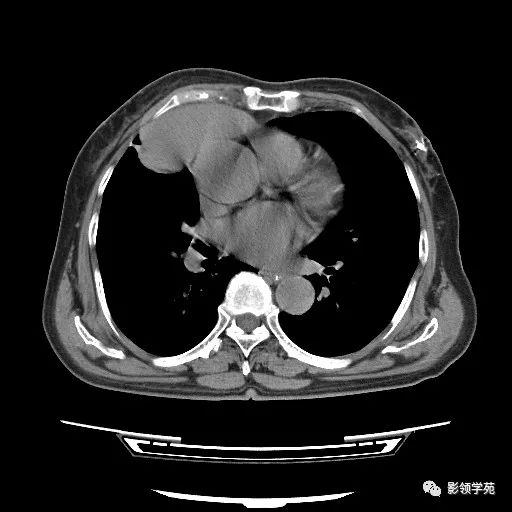

胸腺小细胞癌1例CT

女,72岁,主因进食不畅2月余,查体:T36.1℃ BP145/73mmHg,神清语利,浅表淋巴结未触及肿大,会厌稍充血、水肿,双瞳孔正大等圆,对光光反射灵敏。颈软,无抵抗。双肺呼吸音清,未闻及明显干湿性啰音,心率72次/分,律齐,心音低。腹平软,脐周无压痛,无反跳痛及肌紧张。双下肢无浮肿。四肢肌力、肌张力可。 医学百科网 | YxBaike.Com

病理结果 医学百科网 | YxBaike.Com

胸腺小细胞癌 医学百科网 | YxBaike.Com